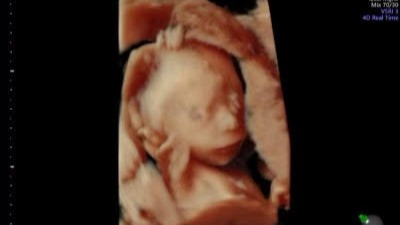

The baby boy (Adrain) has several medical issues, including DS and IUGR. He is very very tiny, <1% of where he should be. There is a very strong possibility that he will not survive to the age of viability, which in his case would be closer to 28 weeks as opposed to 26. Due to these factors, they caution that he might not make it, and might be stillborn, but we know that anything can happen if it's God's will. As of now, even though his dopplers show his cord blood flow is at times reversed, and even periodically absent, he continues to show slight gains... so we pray for his highest and best outcome.. trusting and having faith.

Because this is a twin pregnancy, this puts healthy baby girl (Aliana) at increased risk of everything from premature delivery to also being stillborn. As of now though, she is happy, healthy, growing normally and showing no signs of distress.